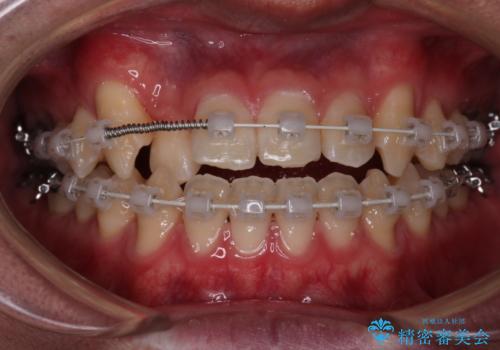

【審美装置】前歯の反対咬合改善

- 前歯の歯並びと噛み合わせを主訴に来院されました。

左右の噛み合わせが反対咬合であることと下顎の皮質骨が薄いため治療計画をしっかりと立てて行う必要のあるケースでした。

その点を考慮して、リンガルアーチを用いて奥歯を遠心移動し、前歯にIPR(歯と歯の間を削る処置)を行うことでスペースを作って歯並びを整えていく計画を立てました。

リンガルアーチを用いて奥歯を遠心移動し、前歯にIPR(歯と歯の間を削る処置)を行うことでスペースを作って歯並びを整えていく計画を立てました。

心配していた歯肉退縮も起こらず、前歯の噛み合わせと歯並びが綺麗に改善されました。

期間も1年2ヶ月と短期間で終了することができ、とても満足度の高い治療になりました。